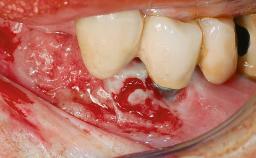

Peripheral Giant-cell Granuloma Associated with Peri-implant Tissues